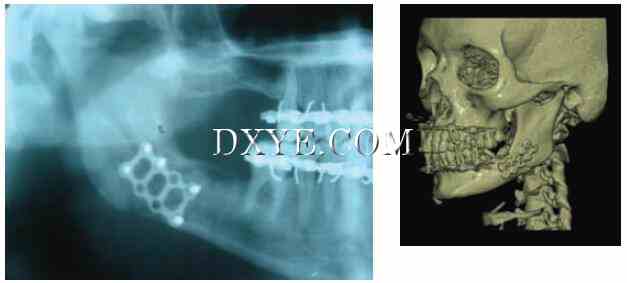

8.jpg

图29.8.  不完全Le Fort I 骨折。 A. 三维计算机断层扫描显示出在Le Fort I级别出现的中点骨折。 B. 该断裂揭示完整的翼板轴位CT扫描。这种骨折在麻醉下检查是完全稳定的,因此不需要稳定。